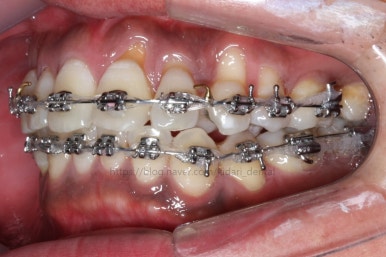

화살표 부분에 원래 송곳니가 있어야 되는데 보이질 않네요. 결손치아일 수도 있고 매복치아일 수도 있겠어요.

왼쪽 위 어금니도 한 개가 없어서 빈공간이 약간 남아있어요.

왼쪽 아래 작은 어금니는 아래쪽으로 많이 꺼져있네요.

이런 경우 X-ray 도 면밀히 관찰해 줘야 합니다.